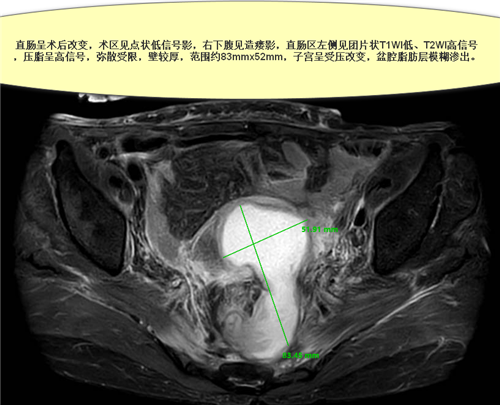

案例2.卞**,87岁女性,于上级医院行直肠癌根治术,因盆腔脓肿,反复腹痛伴发热10天收住胃肠外科,联系我科给予经直肠腔内超声引导下盆腔脓肿穿刺置管引流,引流当天体温即恢复正常。